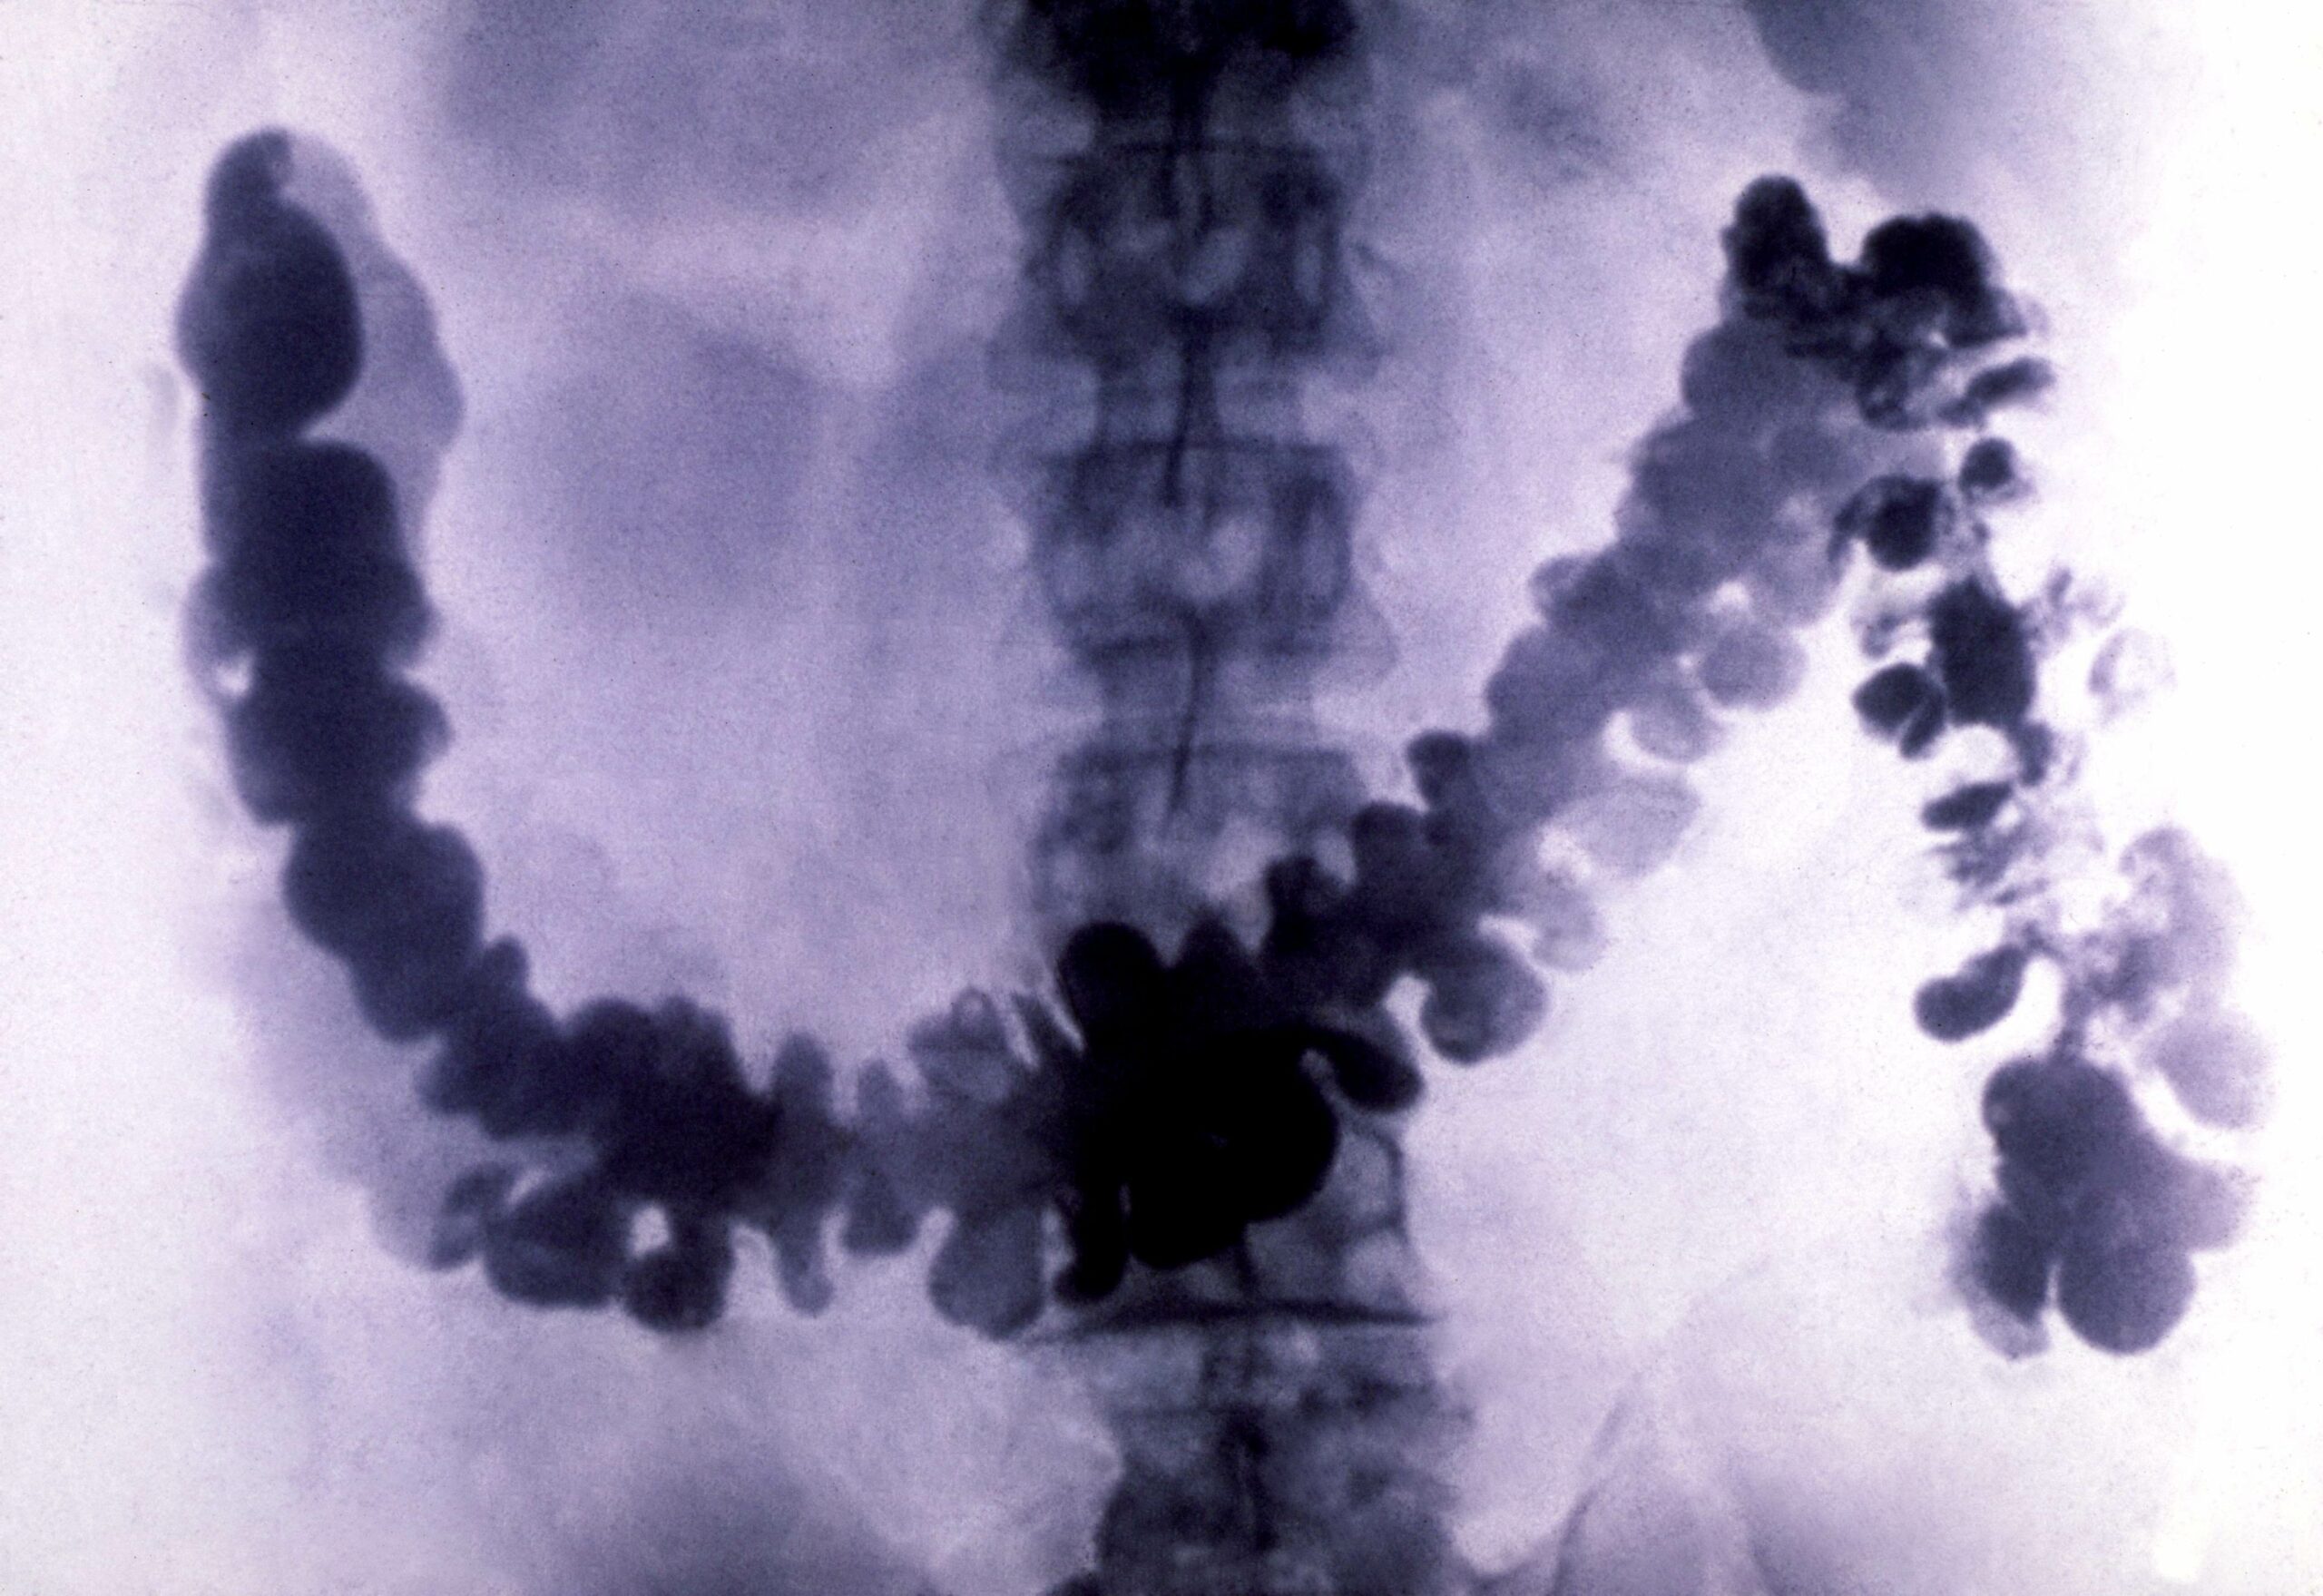

Three percent sounds small, but compounded over time that adds up to many new cases of colorectal cancer. That age group is now back to 1890s-era incidence rates. And since we don’t screen people that young, the outcomes are more likely to be grave—early detection is one of the best ways to head off colorectal cancer. Colonoscopies are relatively easy to do and can find very early stage cancers when they’re still polyps, which are abnormal growths inside the intestines. Polyps aren’t full-blown cancers yet, so you can remove them and prevent the cancer that the polyp might have become.